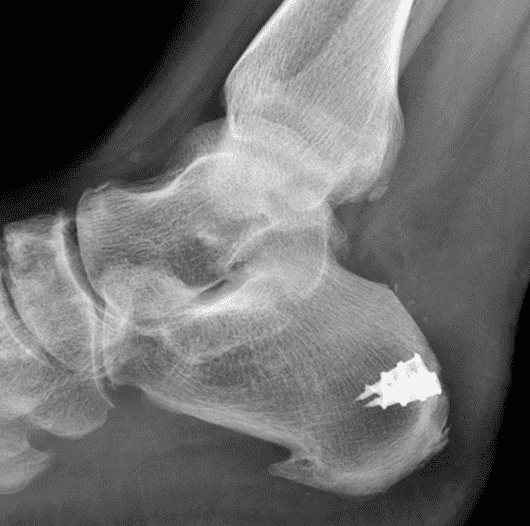

A 22 year-old male college football player presents with a “pop” and pain posterior to the right ankle during practice 1 week prior. He is unable to bear weight. Lateral radiograph (1A), sagittal fat-suppressed T2-weighted (1B), sagittal T1-weighted (1C), and transverse fat-suppressed T2-weighted images are provided. What is your diagnosis? What MRI findings affect clinical management decisions?

Figure 2: Complete Achilles tendon rupture. (2A) The lateral radiograph shows a thick and indistinct proximal Achilles tendon contour (arrows). (2B) A fat-suppressed T2-weighted image shows complete rupture of the tendon with a fluid-filled gap (yellow arrow) measuring 1.5 cm in length, located 10 cm cranial to the tendon insertion (blue arrow) and just distal to the edematous myotendinous junction (red arrow). The tear is superimposed on diffuse tendinosis. (2C) A sagittal T1-weighted image confirms the diffuse tendinosis. Fluid extends anteriorly into Kager’s fat pad (arrow) suggesting disruption of the anterior paratenon. (2D) A transverse fat-suppressed T2-weighted image through the proximal tendon shows no intact fibers (arrow), confirming the full-thickness rupture.

Acute, complete Achilles tendon rupture just distal to the myotendinous junction, superimposed on diffuse tendinosis.